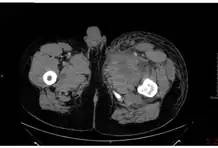

In December 2009, an outbreak of anthrax occurred among injecting heroin users in the Glasgow and Stirling areas of Scotland, resulting in 14 deaths.[23] This became the first documented non-occupational human anthrax outbreak in the UK since 1960.[23] The source of the anthrax is believed to have been dilution of the heroin with bone meal in Afghanistan.[24] Injected anthrax may have symptoms similar to cutaneous anthrax, with the exception of black areas,[25] and may also cause infection deep into the muscle and spread faster.[26] This can cause it to be harder to recognise and treat.

Injection